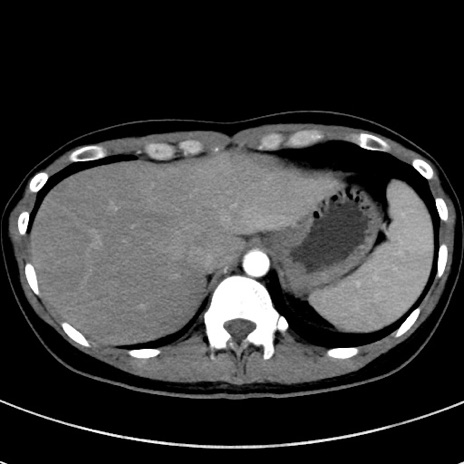

冠状断像

【症例】20歳代女性

【主訴】嘔吐、下腹部痛

【現病歴】昨日夕食後に嘔吐し下腹部痛が出現。本日になっても嘔吐持続し改善しないため来院。

【身体所見】意識清明、BT 37.2℃、BP 108/67mmHg、腹部:平坦、やや硬、下腹部正中から右にかけて圧痛あり、反跳痛軽度あり、tapping pain(+)。

【データ】WBC 13600、CRP 14.94